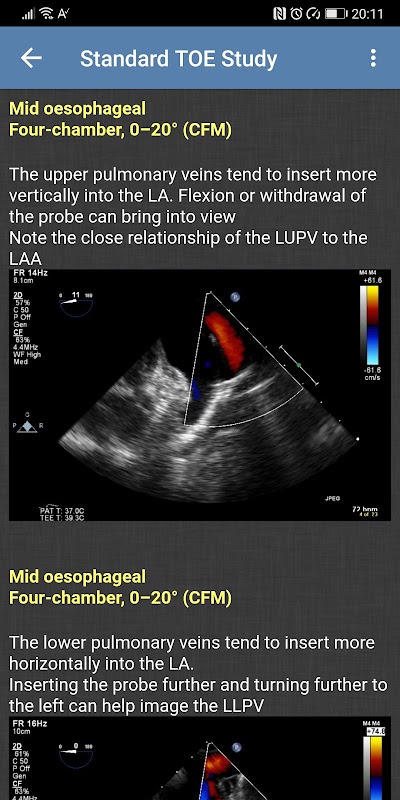

- Estudo TOE Padrão